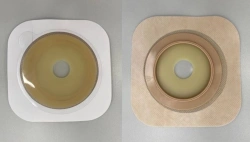

Medical product is intended for use in colostomies, ileostomies and urostomies for hermetic and secure attachment of stoma bags to the skin of the anterior abdominal wall, as well as to protect the skin of the peristomal area from stoma secretions and preserve the physiological functions of the skin due to the absorption of natural skin moisture (sweat, sebum).